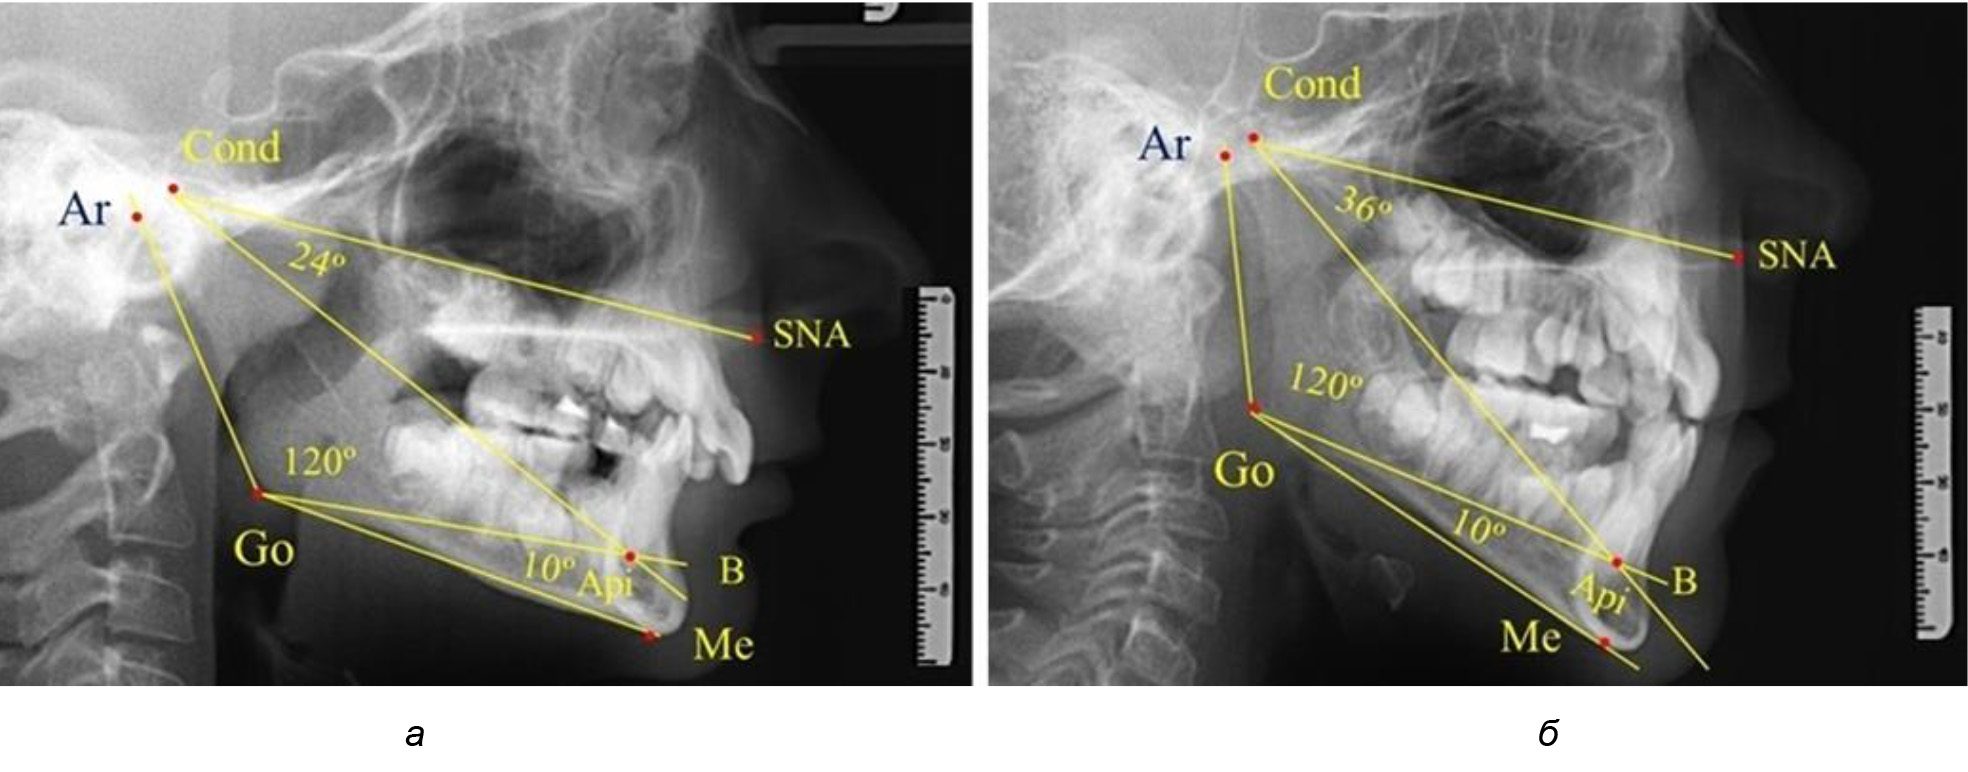

Рис. 5. Варианты ТРГ после прорезывания ППМ и нижних резцов (а), всех резцов и первых премоляров (б)

Таким образом, в периоде молочного прикуса с оптимальными окклюзионными соотношениями, несмотря на линейные размеры в вертикальном и сагиттальном направлении, которые, безусловно, меньше параметров взрослых людей, величина основного угла гнатической части лица SNA-Cond-Api соответствовала параметрам людей с полностью сформированным физиологическим прикусом постоянных зубов. Анализируя данные рентгенограмм детей в периоде сменного прикуса, отмечено, что величина основного угла гнатической части лица SNA-Cond-Api, так же как в молочном и постоянном прикусе, в норме составляла от 28 до 32°. В то же время угол нижней челюсти и его составляющие отличались вариабельностью параметров при различных показателях нижнечелюстного угла. Достоверных различий угла гнатической части после смены нижних медиальных резцов и прорезывания первых постоянных моляров (4 ребенка) не было; происходил очередной этап подъема высоты прикуса и увеличение линейных размеров костей гнатической части, однако угловые параметры были относительно стабильны. После смены всех резцов и замены первых молочных моляров первыми премолярами (6 человек) увеличивались линейные размеры при сохранившихся угловых показателях гнатической части лица (рис. 5).

Таким образом, в период сменного прикуса с оптимальными окклюзионными соотношениями, несмотря на увеличение линейных размеров в вертикальном и сагиттальном направлении, по сравнению с прикусом молочных зубов, величина основного угла гнатической части лица SNA-Cond-Api соответствовала показателям как постоянного, так и молочного прикуса с физиологическими окклюзионными соотношениями.